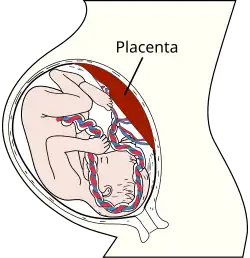

Formation of Placenta

As changes to the endometrium occur, cellular growth and the accumulation of glycogen cause fetal and maternal tissue to come together. This formation makes the functional unit called the placenta. The placenta does not mix blood between mother and fetus, but allows nutrients and waste products to diffuse between the two blood systems. The placenta provides protection by filtering out many harmful substances that the mother comes in contact with. The placenta cannot protect against some teratogens including but not limited to:

Amniotic Fluid

Attached to placenta is the membranous sac which surrounds and protects the embryo. This sac is called the amnion. It grows and begins to fill, mainly with water, around two weeks after fertilization. This liquid is called Amniotic fluid, it allows the fetus to move freely, without the walls of the uterus being too tight against its body. Buoyancy is also provided here for comfort. After a further 10 weeks the liquid contains proteins, carbohydrates, lipids and phospholipids, urea and electrolytes, all which aid in the growth of the fetus. In the late stages of gestation much of the amniotic fluid consists of fetal urine. The fetus swallows the fluid and then voids it to prepare its digestive organs for use after birth. The fetus also "breathes" the fluid to aid in lung growth and development.

- The brain grows much larger, and fatty protective sheath covers the nerve fibers; this important development allows brain impulses to travel faster, enhancing the ability to learn. The lungs have developed most of their airways and air sacs. The placenta is quite selective in what it allows to pass from the mother to the baby's blood, stopping some harmful substances, such as certain drugs, from crossing over.

Umbilical Cord

This is the life support for a growing embryo. The umbilical cord stretches between the placenta and the fetus. This cord contains the umbilical arteries and vein. The umbilical cord forms by week 5 of conception. The average cord is close to 22 inches long and may have the appearance of a coil. The umbilical cord is very rich in stem cells and is often used for parents who choose to store their stem cells in a blood bank or donate it to a blood bank. These stem cells can be used to treat over 45 disorders and is an alternative from extracting the stem cells from a donor.

In many societies' medical and legal definitions, human pregnancy is somewhat arbitrarily divided into three trimester periods, as a means to simplify reference to the different stages of fetal development. The first trimester period carries the highest risk of miscarriage (spontaneous death of embryo or fetus). During the second trimester the development of the fetus can start to be monitored and diagnosed. The third trimester marks the beginning of viability, which means the fetus might survive if an early birth occurs.

- The fetus, placenta, and amniotic fluid account for just over a third of the weight gain during pregnancy. The remaining weight comes from increased blood volume, fluid retention, and extra body fat. The suggested weight gain in most pregnancies is between 25-40 lbs.

The third stage of labor is the delivery of the afterbirth (placenta).

- Placental Abruption is a condition in which the placenta is torn away from the uterine wall causing loss of oxygen and nutrients to the baby, and hemorrhage of mother and baby from the large blood vessels in the placenta. Most women, but not all experience heavy bleeding and abdominal pain. This is a life threatening emergency as a fetus can only survive as long as 50% of the placenta is still attached.